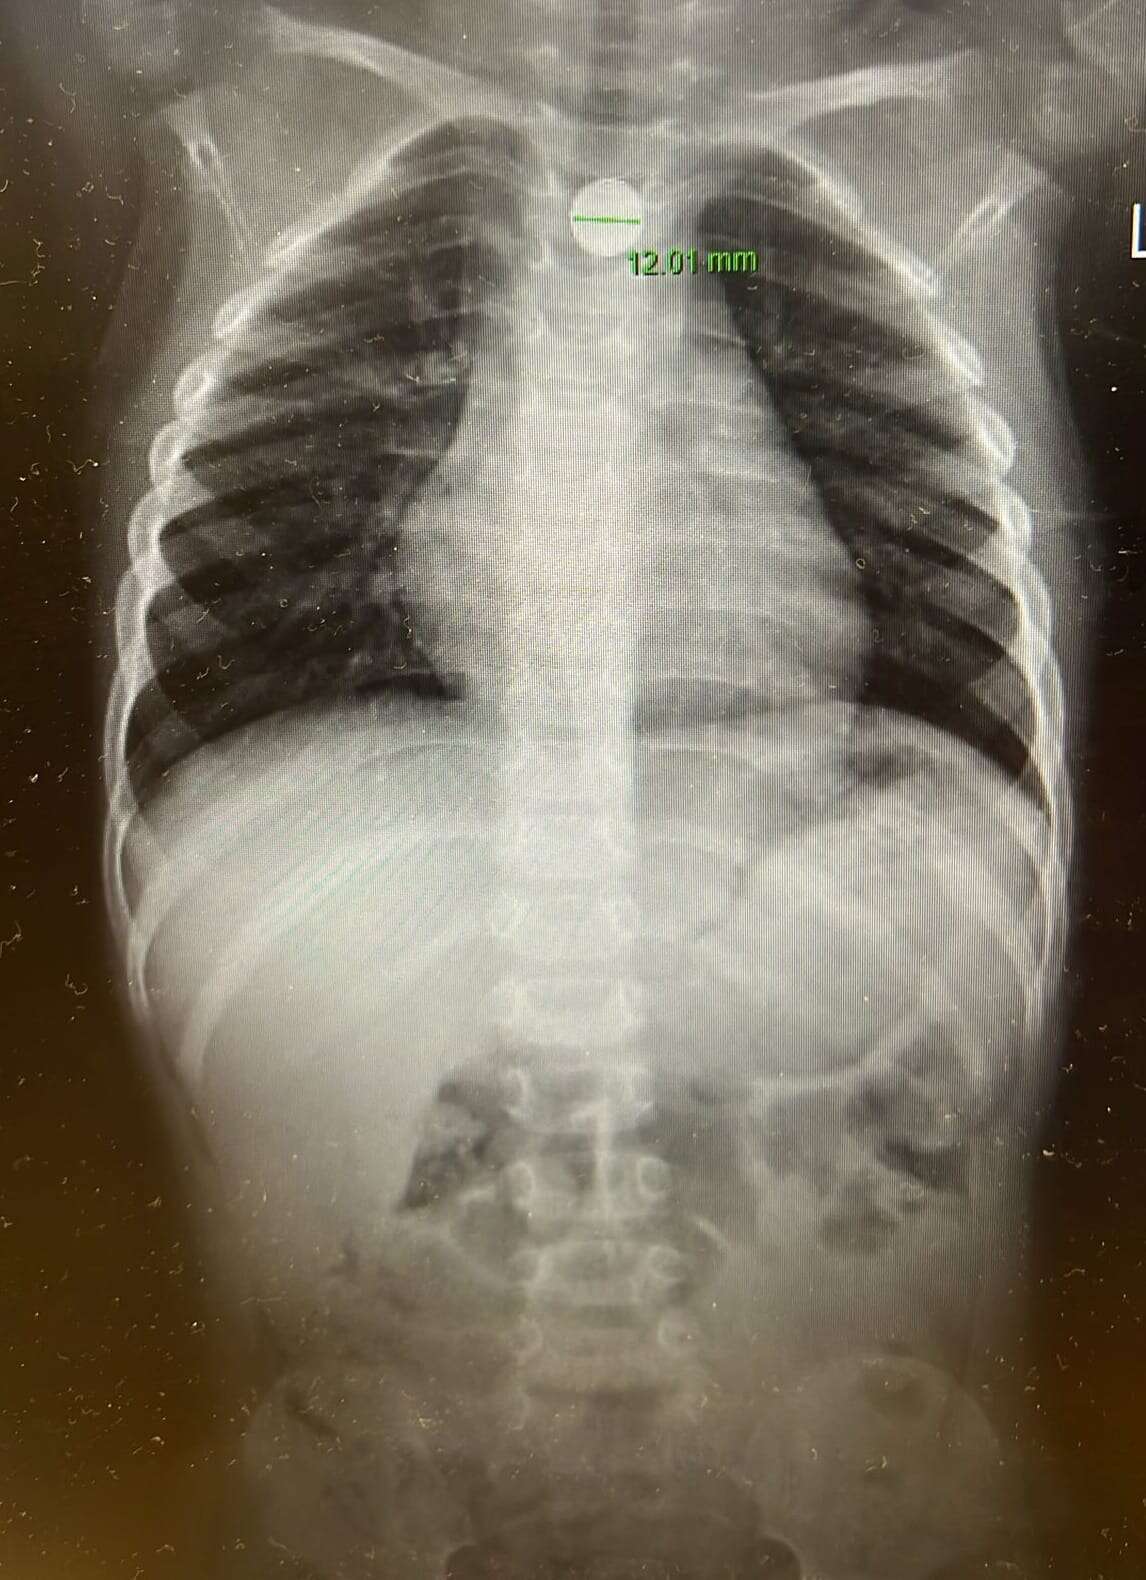

בבית החולים בוצע צילום חזה, בו זוהתה סוללת דיסק התקועה בוושט - ממצא המחייב טיפול דחוף. בעקבות הממצאים הוזעק ד"ר אייל זיפמן, מנהל שירות גסטרואנטרולוגיה ילדים במרכז רפואי מאיר, והוחלט להכניס את הילד במהירות לחדר ניתוח. "הסוללה נמצאה נעוצה בוושט ונשלפה בשלמותה באמצעות גסטרוסקופיה, פעולה אנדוסקופית שבה מכניסים מצלמה דרך הפה לדרכי העיכול העליונות. מסביר ד"ר זיפמן.